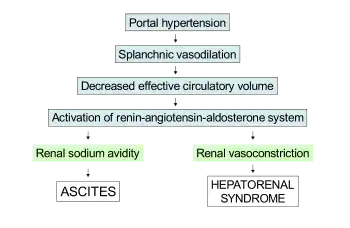

The kidney failure in hepatorenal syndrome is believed to arise from abnormalities in blood vessel tone in the kidneys.[2] The predominant theory (termed the underfill theory) is that blood vessels in the kidney circulation are constricted because of the dilation of blood vessels in the splanchnic circulation (which supplies the intestines), which is mediated by factors released by liver disease.[4][12] Nitric oxide,[13] prostaglandins,[2][14] and other vasoactive substances[2] have been hypothesized as powerful mediators of splanchnic vasodilation in cirrhosis.[2] The consequence of this phenomenon is a decrease in the "effective" volume of blood sensed by the juxtaglomerular apparatus, leading to the secretion of renin and the activation of the renin–angiotensin system, which results in the vasoconstriction of vessels systemically and in the kidney specifically.[2] However, the effect of this is insufficient to counteract the mediators of vasodilation in the splanchnic circulation, leading to persistent "underfilling" of the kidney circulation and worsening kidney vasoconstriction, leading to kidney failure.[12]

The underfill theory involves activation of the renin–angiotensin–aldosterone system, which leads to an increase in absorption of sodium from the kidney tubule (termed renal sodium avidity) mediated by aldosterone, which acts on mineralocorticoid receptors in the distal convoluted tubule.[8][12] This is believed to be a key step in the pathogenesis of ascites in cirrhotics as well. It has been hypothesized that the progression from ascites to hepatorenal syndrome is a spectrum where splanchnic vasodilation defines both resistance to diuretic medications in ascites (which is commonly seen in type 2 HRS) and the onset of kidney vasoconstriction (as described above) leading to hepatorenal syndrome.[8]